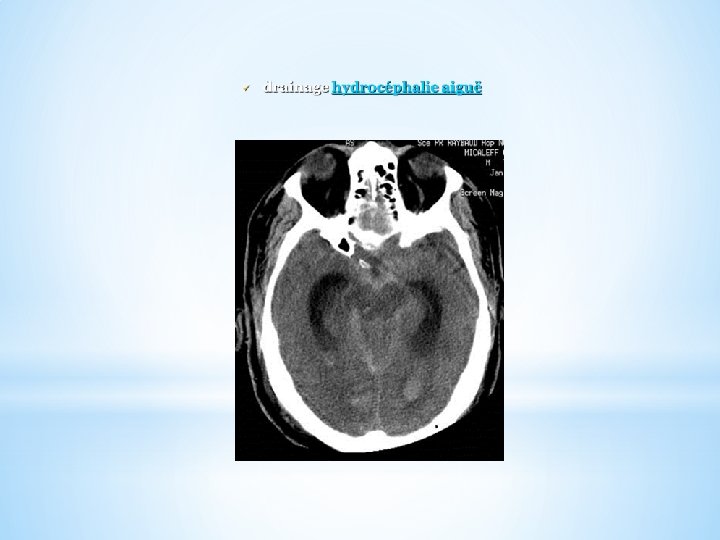

+ Drainage LCR : si échec des mesures générales ( PIC à la limite sup des objectifs) + Traitement spécifique d’HTIC : - Mannitol - Hyperventilation Pa. CO 2=30 -35 ( surveillance DSC et SVj. O 2) + Traitement HTIC réfractaire Barbituriques ( thiopental) +ou- Hypothermie modérée hyperventilation profonde Pa. CO 2 inf 30 mmhg HTA induite SSH Craniotomie / Craniectomie decompressive